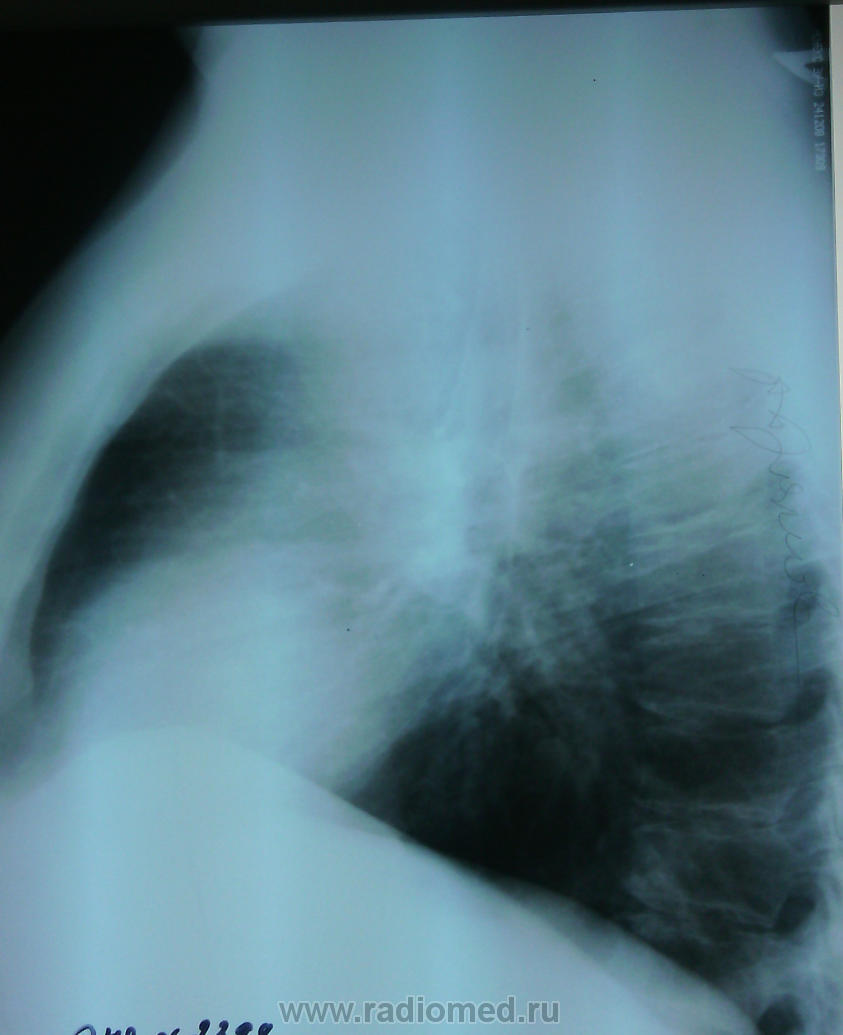

м, 43, СДиабет. Меня смущает тень около дуги аорты слева. Грудина вроде накладывается на тень. Буду благодарна мнениям )

Эта тень живёт своей жизнью. Находится парамедиастинально. У меня три версии: увеличенный лф/узел , туберкулома (правда, такой формы не встречала ни в жизни, ни в литературе) или ретенционная киста .

Не знаю о чем вы? Возможно левый паратрахеальный лимфоузел. Но, если у вас просто с КТ, направляйте, СД - группа риска по ТВС.

Не просто паратрахеальный, а левый паратрахеальный. Ну, а дальше, пишите как привыкли, мой вариант "рек. дообследование на предмет активности туб процесса", ваш "рек. консультация фтизиатра". Мой (на мой взгляд) строже. Что толку, если фтизиатр ограничится осмотром?

Может также быть артроз грудино-ключичного сочленения, а так КТ желательно.